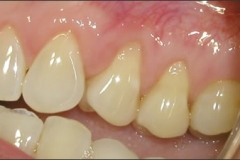

This mouth had recession on just one tooth with very little bone to support the tooth. The area needed support and thickness. The tissue was placed and the area now has thicker tissue to withstand the forces that the patient needs to place on it.